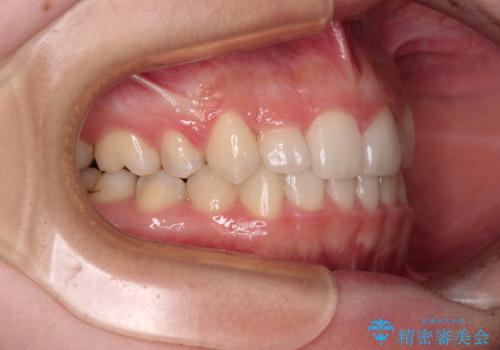

- 前歯のデコボコと八重歯を気にして来院された患者様です。

目立たない装置を希望されたので、上顎が裏側装置のハーフリンガルを選択し、左右上顎小臼歯1本ずつを抜歯して、矯正治療を行うこととしました。

治療期間の目安は2年半~3年間でしたが、予定通り治療が進み、2年半弱で終えることができました。

歯列はきれいに整い、治療期間も予定通りであり、患者様には大変満足していただきました。